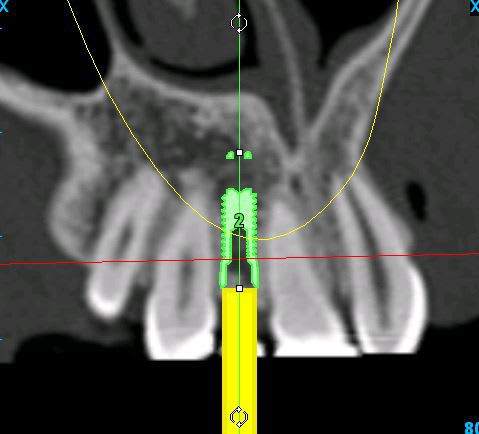

je mets les coupes et les radios post op...

intervention "quasi" flaless, juste des incisions crestales en W pour manager les papilles...